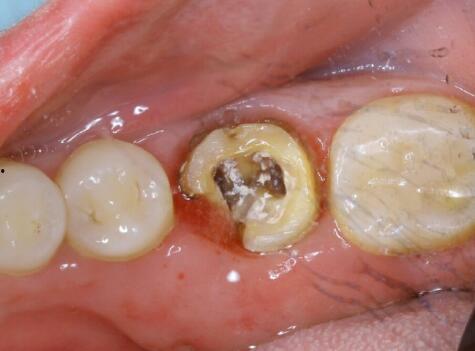

1. 牙根的“真实面目”:原来,烂牙根竟然如此复杂,错综复杂地缠绕在牙槽骨中。

3. 拔牙过程的“惊险”:医生在拔牙过程中,需要克服牙根的顽强抵抗,稍有不慎,就可能伤及周围组织。

看着视频中的医生和护士,我们不禁为他们的专业和耐心点赞。而患者,也在经历了一场视觉与心理的双重挑战后,成功摆脱了烂牙的困扰。